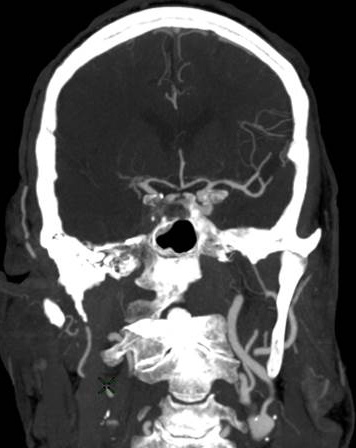

Figure 1: Ischemic Stroke. In an early acute ischemic cerebral stroke, a common finding is a normal CT scan since the brain tissue has not yet begun showing ischemic changes (left image). The middle image shows a diffusion weighted image (DWI) of a right hemispheric stroke (white area), and a CT angiogram shows the cause to be a blockage of the right middle cerebral artery (MCA), seen as a lack of blood vessel flow on the right side of the brain (left side of image). Poor blood flow is also seen in the right internal carotid artery due to stenosis from atherosclerosis. (Images courtesy of Dr. McMurtrey)